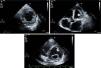

Isolated left ventricular noncompaction (LVNC) is a form of cardiomyopathy resulting from persistence of fetal trabeculations and intertrabecular recesses within ventricular myocardium. The clinical features associated with LVNC consist of left ventricular (LV) systolic dysfunction, arrhythmias, and thromboembolic events. We report the case of a 67-year-old woman admitted to the emergency department with acute aphasia, dyspnea, and peripheral edema associated with recent-onset paroxysmal atrial fibrillation (AF) with high ventricular rate. After anticoagulation with unfractionated heparin (UFH), she was converted to stable sinus rhythm with intravenous (IV) amiodarone. She was then admitted to the intensive coronary care unit (ICCU) and treated with IV inotropes and diuretics, resulting in prompt recovery from aphasia and improvement in congestion. The echocardiogram showed a markedly dilated left ventricle with hypertrabeculation of the apex and of the inferior-inferolateral segments (noncompacted/compacted ratio 2:1), severely reduced ejection fraction (EF) (22%), and an apical thrombus. No significant carotid artery disease was found on Doppler echocardiography. She underwent implantation of an implantable cardioverter-defibrillator and was discharged in NYHA class II, under standard heart failure therapy including oral anticoagulation (OAC), with no evidence of thrombosis (Figure 1). Twelve months later, due to a major depressive episode, the patient failed to attend the scheduled heart failure clinic (HFC) follow-up and discontinued OAC. Due to recurrent dyspnea and fatigue she presented to the HFC, where an echocardiogram showed a massive LV thrombosis (Figure 2), so she was admitted to the ICCU and IV UFH was started. After two days the patient complained of chest pain; as the ECG showed marked ST segment elevation in V3-V6 she was referred to the catheterization lab. Coronary angiography revealed a thrombotic occlusion of the mid segment of the left anterior descending artery (Figure 3A); the clot was aspirated and no significant coronary artery disease (CAD) was found (Figure 3B and C). A marked increase in plasma troponin I was observed, confirming the diagnosis of acute embolic myocardial infarction (MI). Her EF fell to 15% and after two days she became hypotensive despite intra-aortic balloon pump and inotropic support, with cardiogenic shock and acute kidney failure. She was considered for a left ventricular assist device, but sepsis and multiorgan failure occurred, and death followed 25 days later.

(A) Parasternal short-axis view of the mid segments. Two-layered structure of the thickened myocardium, with deep trabecular recesses in inferior, inferolateral and anterolateral segments; (B) apical 5-chamber view showing a floating thrombotic mass; (C) parasternal short-axis view showing thrombotic masses in the basal and mid segments of the anterior wall of the left ventricle.